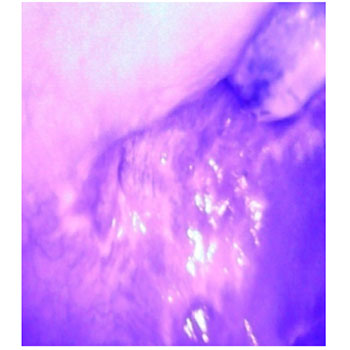

CASE OF PIGMENTATION

CLINICAL IMAGE

AFTER FILTERING

IMAGE WITH INFLUENCE OF BLUE LIGHT AFTER FILTERING